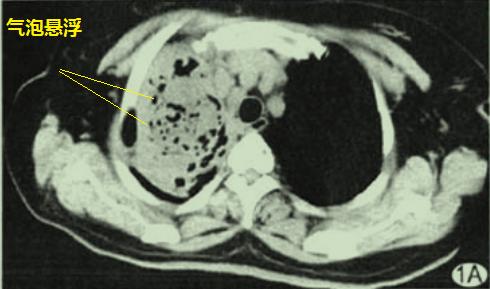

图1是典型的肺脓肿,空洞内有气液平!牛顿万有引力的基本原理告诉我们,气往高处走,液往低处流,于是乎形成了气液平。

图1 肺脓肿

图1 肺脓肿2

肺部空洞悬浮气泡征(图2),简单的说就是反常的存在,不把牛顿万有引力放在眼里(从表面上看):气体的分布与重力无关,不形成气液平,空气悬浮在液体里面。

图2 肺部空洞悬浮气泡征

图2 肺部空洞悬浮气泡征这个患者的病理是什么呢?

揭晓答案:放线菌感染(图3),空洞悬浮气泡征高度提示肺部放线菌病。

图3 放线菌感染

图3 放线菌感染图4也是肺部空洞悬浮气泡征,最终诊断也是肺部放线菌病。

图4 肺部空洞悬浮气泡征为什么肺放线菌病空洞内的空气会违反牛顿万有引力呢?有学者推测,对于肺放线菌病,空洞内低密度无强化的物质,其实是坏死组织+大量放线菌+硫磺颗粒,流动性差;空洞内的气体密度影,可能是含硫磺颗粒、放线菌的微脓肿,或是残存的扩张支气管。由此可见,空洞内的液体难以流动,气体也不容易流动,所以不会形成气液平。